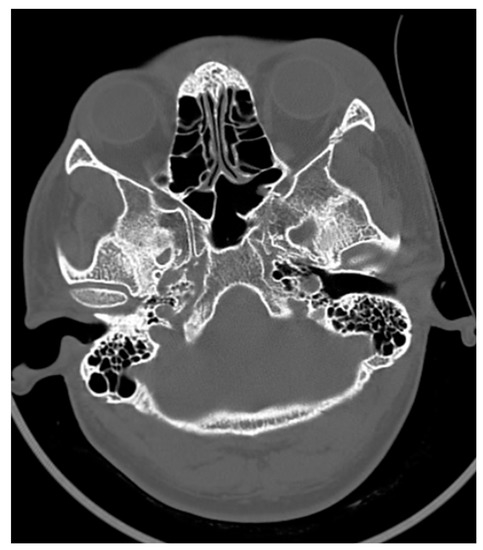

In a case of zygomatic complex fracture, orbital involvement revealed a linear minimally displaced fracture noted involving the left zygomatic arch, the lateral wall of the left orbit. A comminuted displaced fracture involving the lateral wall of the left maxillary sinus with fracture fragments lying inside was associated with hemosinus (Figure 4 and Figure 5). However, the soft tissue window failed to reveal further details with regard to the pterygoid muscles and orbital volume. Other than the displacement and type of fractures, the extent of orbital involvement also determines surgical treatment in this case. The most common cause of posttraumatic enophthalmos is increased orbital volume [6]. All images were taken using 5th generation mono-energy CT machines with standard exposure parameters of 140 kvp, 200 mA soft tissue with a slice thickness of 0.5–0.6 mm, and bony windows.

Figure 4. CT axial section of a pan-facial trauma: a comminuted displaced fracture involving the lateral wall of the left maxillary sinus with fracture fragments lying inside, associated with hemosinus.

Figure 5. Comminuted displaced fracture involving the lateral wall of the left maxillary sinus with fracture fragments lying inside, associated with hemosinus. The soft tissue window failed to reveal further details with regard to the pterygoid muscles and orbital volume.